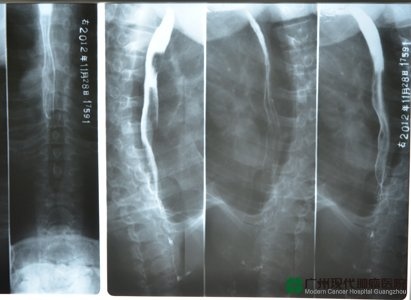

วันที่ 22 เดือนสิงหาคมปี 2555 คุณเฉินมาถึงกวางโจวพร้อมกับภรรยาของเขา อาการเขาสาหัสมากจนทำให้การตรวจร่างกายอย่างรอบด้านถูกขัดขวาง เพราะหลอดอาหารถูกเนื้องอกปิดกั้นจนแคบมาก ไม่สามารถทำการส่องกล้องตรวจหลอดอาหารได้ งั้นควรทำอย่างไรดี หมอที่มีประสบการณ์สมบูรณ์ใช้หลอดอันหนึ่งทำให้หลอดอาหารค่อย ๆ ขยายใหญ่ขึ้น แล้วทำการตัดเนื้อออกตรวจและการตรวจแบบอื่น และยังทำการถ่ายภาพรังสีส่วนตัดอาศัยคอมพิวเตอร์ (CT Scan) ด้วย คุณเฉินถูกวินิจฉัยว่าเป็นมะเร็งหลอดอาหารส่วนบนชนิด squamous cell carcinoma และเซลล์มะเร็งแพร่กระจายไปยังต่อมน้ำเหลืองประจันอก (mediastinum) ในครั้งแรกที่เข้าพักโรงพยาบาลซึ่งเริ่มจากวันที่ 1 เดือนกันยายนถึงวันที่15 เดือนตุลาคมปี 2555 คุณเฉินได้รับการอุดเส้นเลือดเฉพาะจุดสามครั้งและการฉายรังสีหลายครั้ง

ผลการผ่าตัดเหล่านี้เป็นอย่างไร หนึ่งเดือนผ่านไป ในวันที่ 25 เดือนพฤศจิกายนปี 2555 คุณเฉินมาตรวจร่างกายครั้งใหม่ที่โรงพยาบาลพร้อมกับภรรยา คุณถังบอกเขาว่า “ คุณฟื้นตัวได้ดีมาก เนื้องอกหายไปแล้วซึ่งเป็นขนาดใหญ่ 5 ซม. ในครั้งแรกที่เข้าพักโรงพยาบาล ”คุณถังยังถามถึงสถานการณ์ชีวิตประจำวันของคุณเฉิน “ หลังการขยายหลอดอาหารหนึ่งสัปดาห์แล้วเขาก็สามารถรับประทานอาหารได้นิดหนึ่งได้อย่างช้า ๆ ตอนแรกเป็นโจ๊ก แล้วก็เป็นบะหมี่ จนสุดท้ายรับประทานข้าวได้ ” เมื่อภรรยาคุณเฉินคุยถึงการฟื้นตัวของคุณเฉิน หน้าเธอก็เต็มไปด้วยรอยยิ้ม “เมื่อก่อน เวลาดื่มน้ำเขาก็จะสำลัก อาหารต้องปั่นให้เหลวจึงรับประทานได้ ปัจจุบันนี้ก็นอนหลับสบายมาก น้ำหนักก็กลายเหมือนเดิมแล้ว”

คุณถังอธิบายว่า ตอนแรกหลอดอาหารถูกเนื้องอกปิดกั้น จากเครื่อง CT Scan ก็เห็นว่าเหลือแต่ช่องที่แคบมาก ผลการตรวจร่างกายครั้งใหม่ในวันที่ 28 พฤศจิกายนพบว่า หลอดอาหารกว้างเหมือนเดิมและเนื้องอกก็หายไปแล้ว